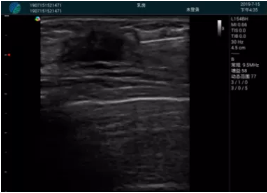

清晰顯示腺體內(nèi)低回聲快影,邊界清晰,包膜較光滑

確定進針路徑并實時監(jiān)測抽吸針與腫塊位置關(guān)系

抽吸針進入腫塊內(nèi)部進行旋切

抽吸過程中可見腫塊明顯縮小,并根據(jù)腫塊位置改變針道位置

抽吸旋切后再進行超聲復(fù)查,原腫塊區(qū)域未見殘留組織及出血